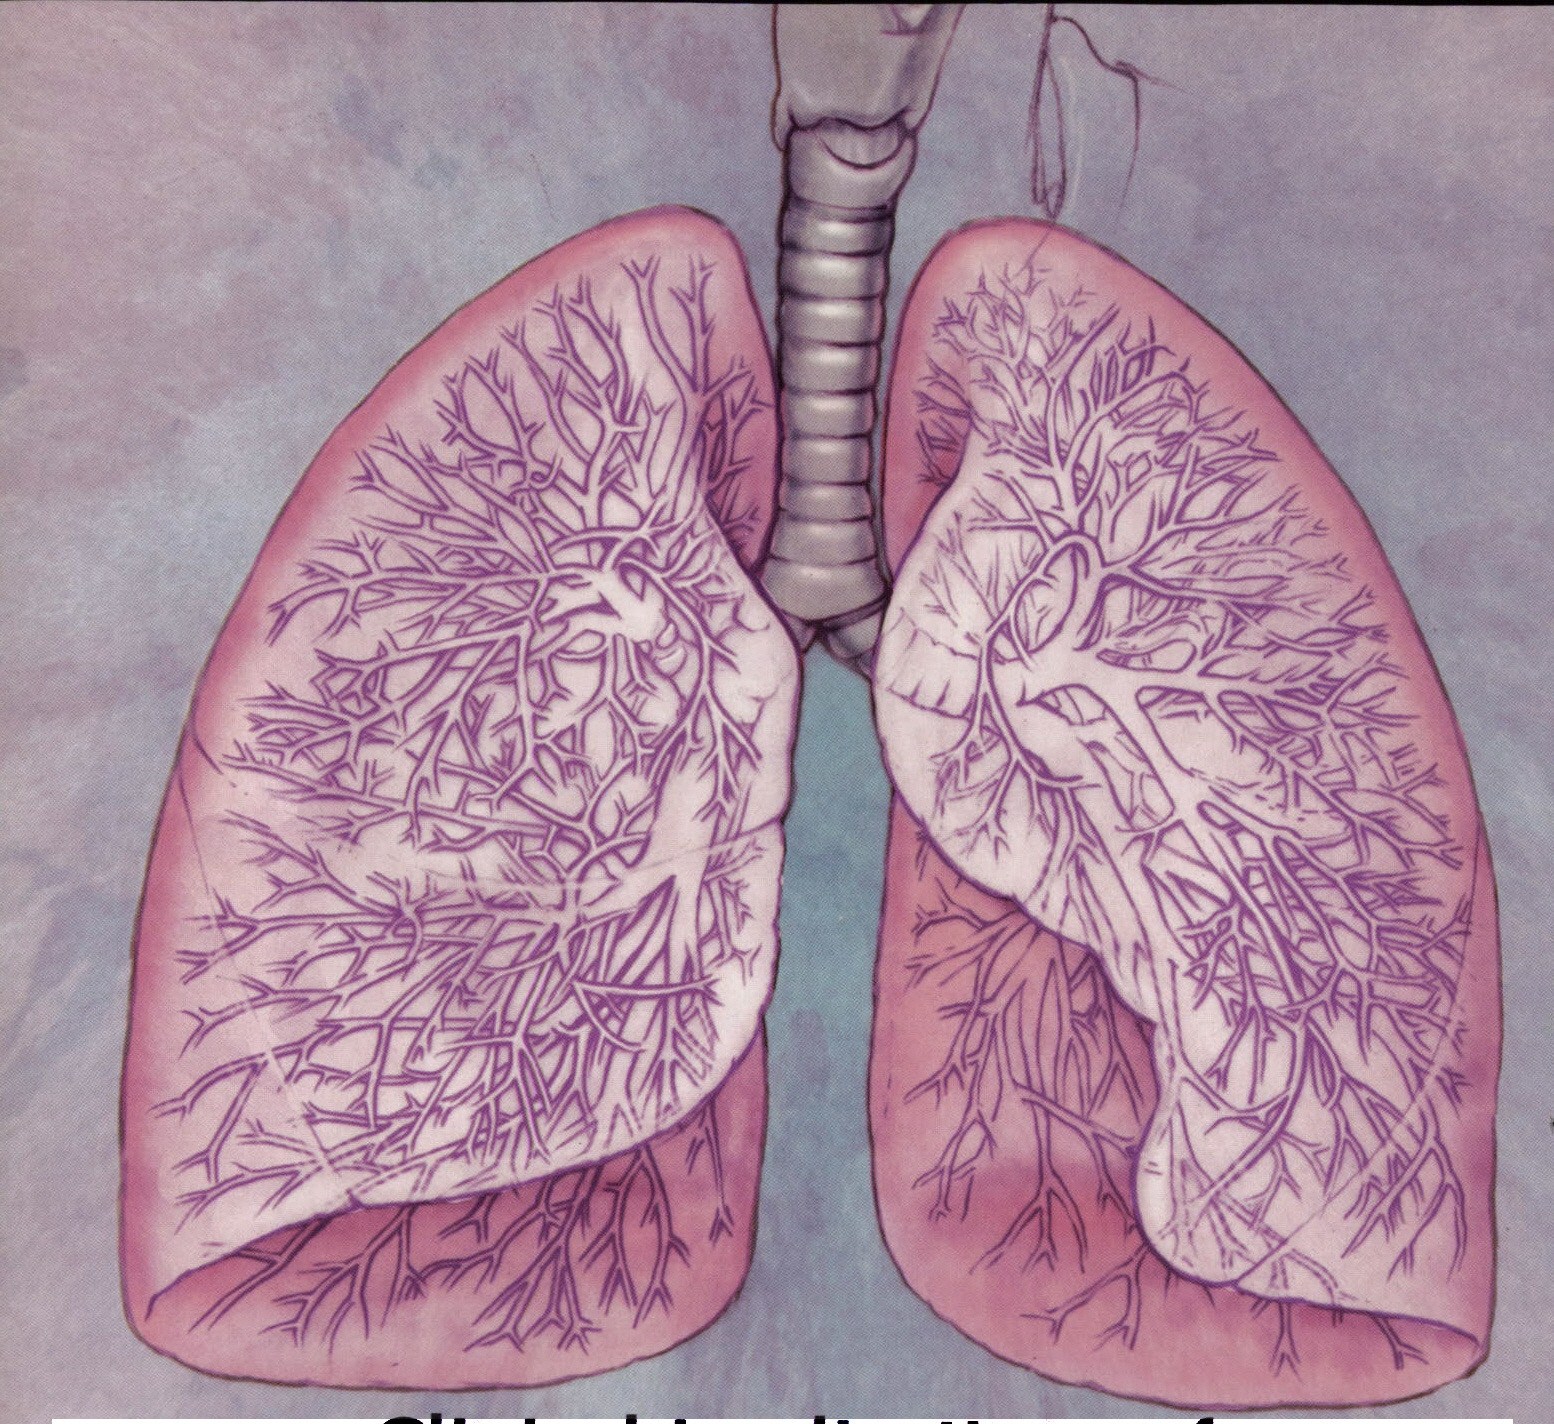

Здоровье дыхательной системы: бронхи и легкие